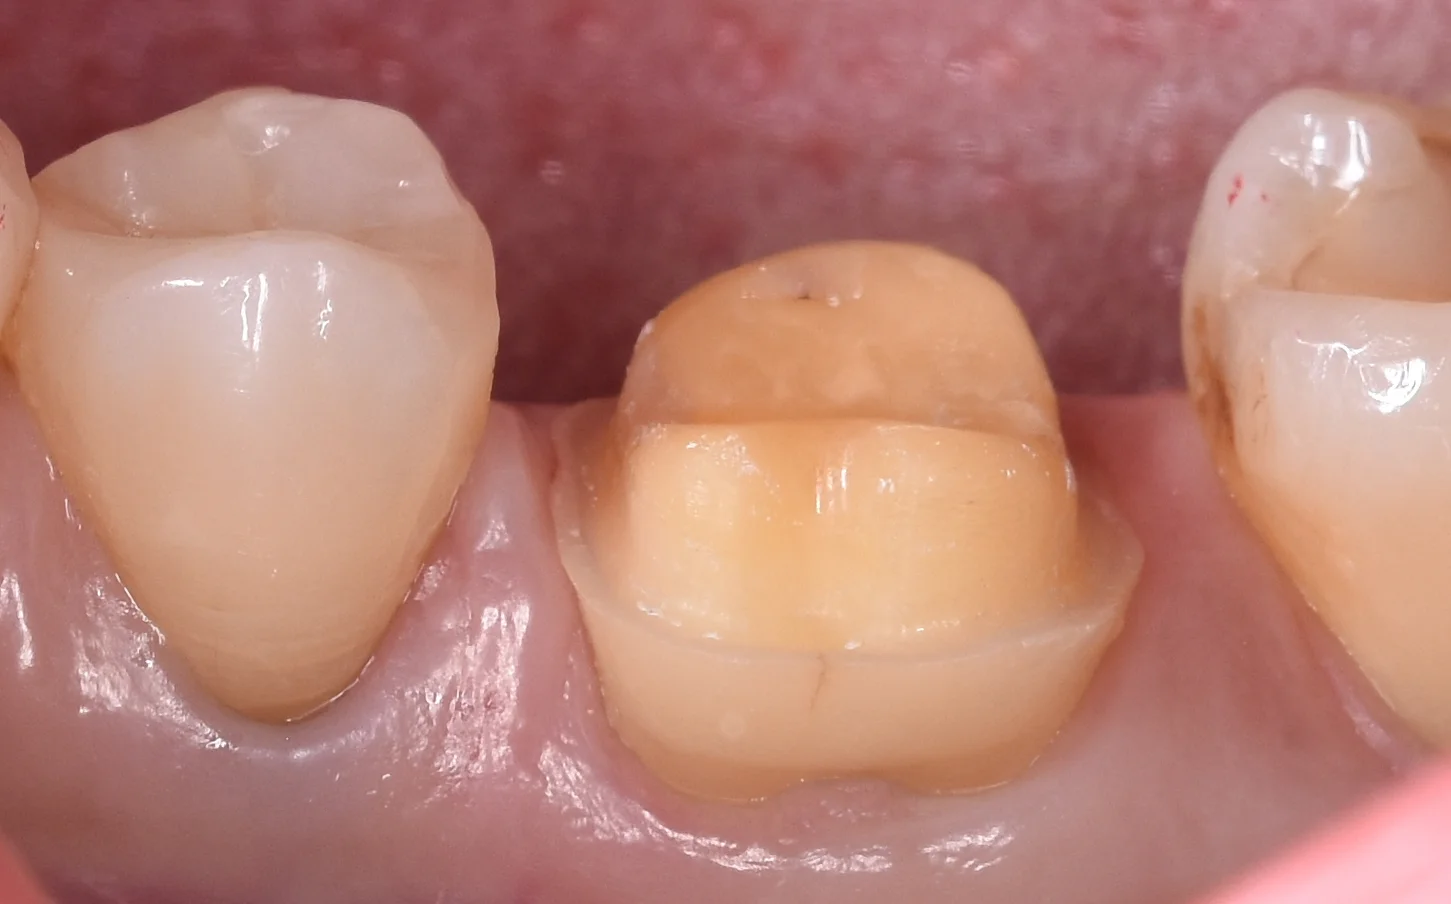

術前の状態からです。

術前というより形作りして型取りする直前の状態ですね。

基本的にセラミックは全周綺麗に厚みが取れるようにしておかないと噛む力を支えられずにセラミックが割れてしまいます。

そのため、こういう感じで全体的に大きく削る必要が出てきます。

今回は金属の詰め物を詰めた歯に亀裂が入ってしまい、その結果噛むと痛むという症状が出てしまっていました。

通常であれば歯の温存を考えるとこういうケースでは金属の方が有利なのですが、下の奥歯で口を開くと普通に見えてしまう場所だったため、セラミックを希望されました。

側面からの写真がこちらになります。